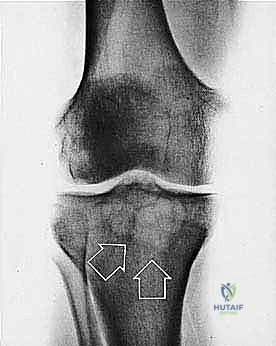

* الساركوما العظمية (Osteosarcoma): الأكثر شيوعاً، تظهر عادة حول الركبة (أسفل الفخذ أو أعلى القصبة).

تحديد مراحل الورم (Staging): نظام Enneking

تحديد مرحلة الورم هو الخطوة الأهم قبل أي تدخل جراحي. يعتمد الدكتور هطيف على نظام (Enneking) لتحديد مراحل أورام العظام، والذي يعتمد على ثلاثة عوامل:

2. الموقع (Site - T): هل الورم داخل الحيز العظمي (Intracompartmental - T1) أم اخترق القشرة وخرج للحيز الخارجي (Extracompartmental - T2)؟